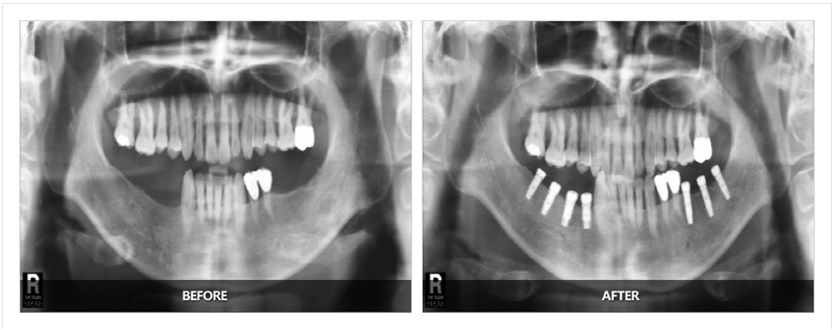

前沿拓展:種植牙基臺(tái)應(yīng)該漏出多少

拓展知識(shí):種植牙基臺(tái)應(yīng)該漏出多少